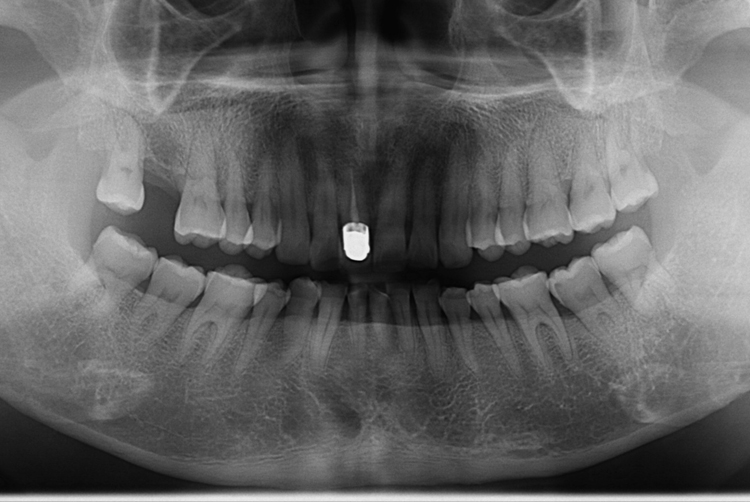

[임플란트] 어금니 임플란트

치료후 : 2017-08-31

세종치과는 많은 환자와 다양한 케이스를 바탕으로

항상 편안한 임플란트 수술을 제공하고자 노력하고,

오래동안 튼튼히 쓸 수 있는 임플란트 수술을 가장 큰 목표로 삼고 있습니다.